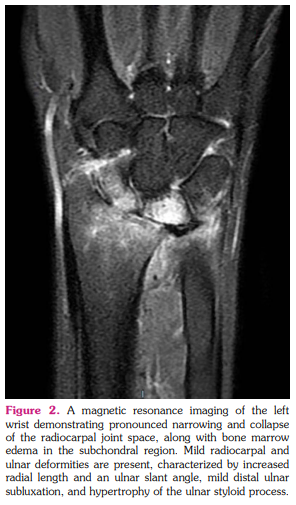

An X-ray of the left wrist (Figures 1a, b) revealed significant narrowing and collapse of the radiocarpal joint space, accompanied by surface irregularities, subchondral sclerosis, and subchondral cyst formation. No posttraumatic bone fractures were detected, and the soft tissues appeared normal. Subsequent imaging with MRI showed a further increase in the pronounced narrowing and collapse of the radiocarpal joint space, along with bone marrow edema in the subchondral region. Osteophytes were detected, along with subchondral cystic changes. Notably, marked synovitis was observed in the radiocarpal and distal radial ulnar joints. Mild radiocarpal and ulnar deformity was present, characterized by increased radial length and an ulnar slant angle, mild distal ulnar subluxation, and hypertrophy of the ulnar styloid process, consistent with the features of Madelung's deformity (Figure 2).